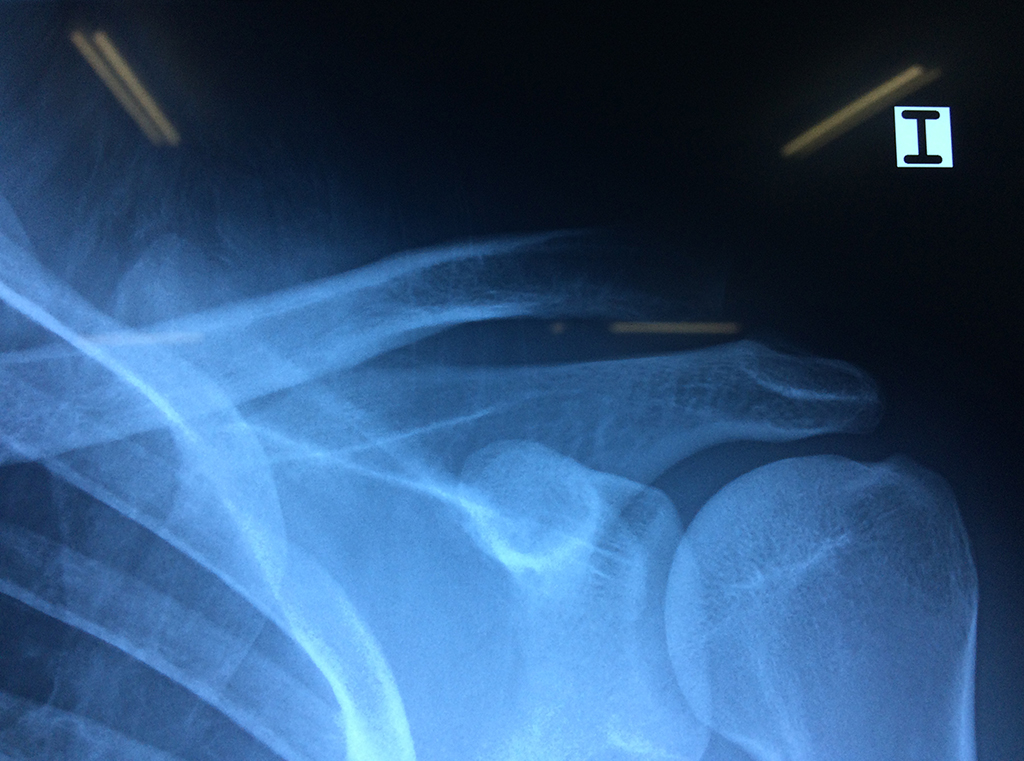

La principal articulación del hombro es la que une la cabeza del húmero con la escápula, recibe el nombre de articulación escapulohumeral y presenta dos superficies articulares, una de ellas corresponde a la cabeza del humero que tiene forma semiesférica y la otra es la cavidad glenoidea de la escápula, estas superficies están recubiertos por cartílago que permiten un movimiento suave e indoloro.

Exteriormente una envoltura de tejido blando circunda el conjunto, es la llamada cápsula articular que está reforzada por varios ligamentos que le dan estabilidad e impiden que los huesos se desplacen más allá de sus límites fisiológicos. Un conjunto de músculos y sus tendones se unen a las superficies de los huesos y hacen posible la movilidad de la articulación, entre ellos es muy importante el manguito rotador formado por cuatro músculos que proporcionan movilidad y estabilidad al hombro.